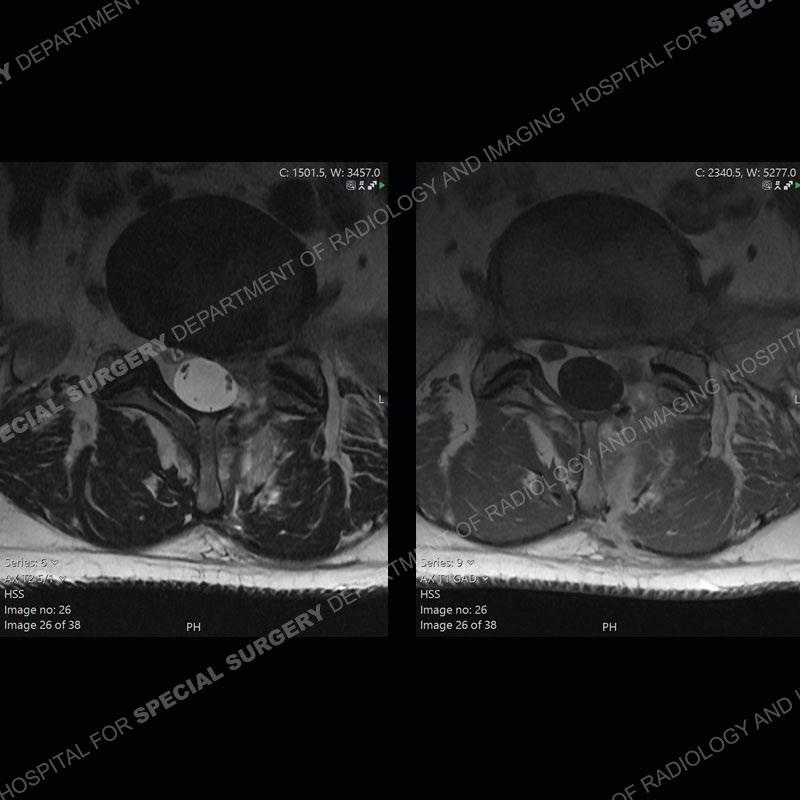

Post operative changes are seen on the left side at L5-S1 where there is near complete removal of the left sided L5 lamina, partial resection of the left L5-S1 facet joint, and resection of the left sided ligamentum flavum. In the anterolateral epidural space about the subarticular recess is a mass that demonstrates similar T1 and T2 signal characteristics to the adjacent degenerated disc. There is enhancement about the periphery of the mass, but the majority of this somewhat geographic or polyploid mass demonstrates no enhancement. The mass exerts prominent mass effect on the left S1 axillary sleeve/proximal nerve root. The left S1 nerve root shows enlargement and increased enhancement as compared to the contralateral right side.

Diagnosis: Recurrent Disc Herniation

Not as much of a diagnostic dilemma as some other cases but more so just a very nice example of what can be a difficult assessment at times. The evaluation of granulation tissue/scar/epidural fibrosis vs. disc herniation particularly in the earlier post operative period can be very difficult. Clues that can assist in identifying a disc herniation are a more geographic or polypoid nature to the mass, signal characteristics similar to the adjacent degenerated disc, mass effect upon the thecal sac/adjacent neural structures, and a typical enhancement pattern. As the disc material is avascular, as long as imaging is performed in a relatively rapid fashion after contrast administration (within 20-30 minutes), the granulation tissue around the disc will enhance but the disc material itself will not. If there is a marked delay between contrast administration and imaging, there may be diffusion of contrast into the disc making the assessment very difficult. The marked utility of contrast to help delineate disc vs. scar has led to our institution employing contrast fairly uniformly within the first two years following surgery.